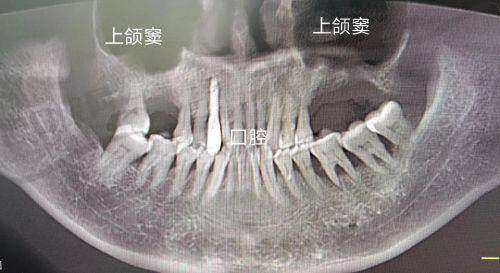

由于上颌窦与鼻腔相通,术后常出现:

单侧鼻塞:持续5 - 10天

血性分泌物:前3天较明显

鼻腔异物感:可能持续2 - 3周

临床统计显示,约30%的患者在术后10 - 15天会出现短暂的鼻塞加重现象,这通常是愈合过程中的正常反应,不必过度担心。